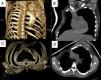

Tomografía computarizada torácica y 3DAgenesia de músculos pectorales mayor y menor derechos. Anomalías costales ipsilaterales, con hipoplasia del tercer, cuarto y quinto arcos costales. Hipoplasia de pulmón derecho y glándula mamaria derecha. Rama arterial anómala, que procede de la aorta abdominal e irriga el segmento posterobasal del lóbulo inferior derecho (hallazgo confirmado por angio-TC) (fig. 1).